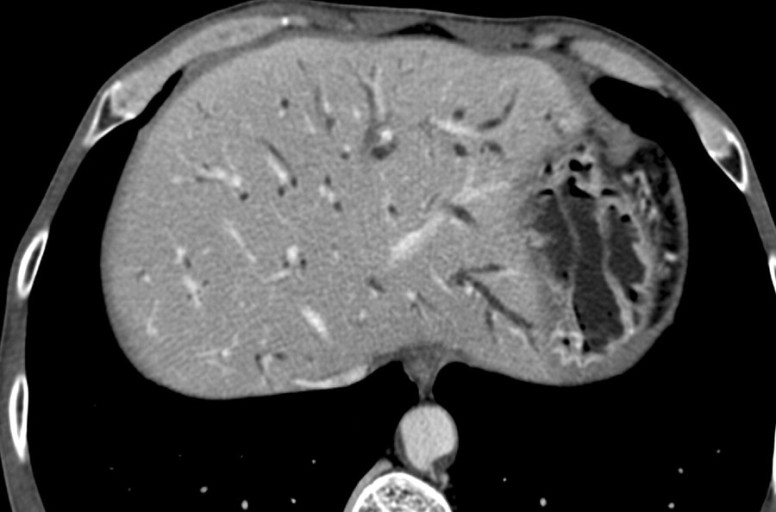

간흡충증은 간흡충이라는 기생충에 의해 발생합니다. 간흡충은 생선을 매개체로 하며, 감염된 생선을 섭취하면 간흡충증에 걸릴 수 있습니다. 간흡충증은 전 세계적으로 분포하며, 특히 동남아시아, 중국, 한국 등에서 흔히 발생합니다.

간흡충증의 원인은 간흡충이라는 기생충입니다. 간흡충증은 생선을 매개체로 하며, 다음과 같은 과정을 통해 감염됩니다.